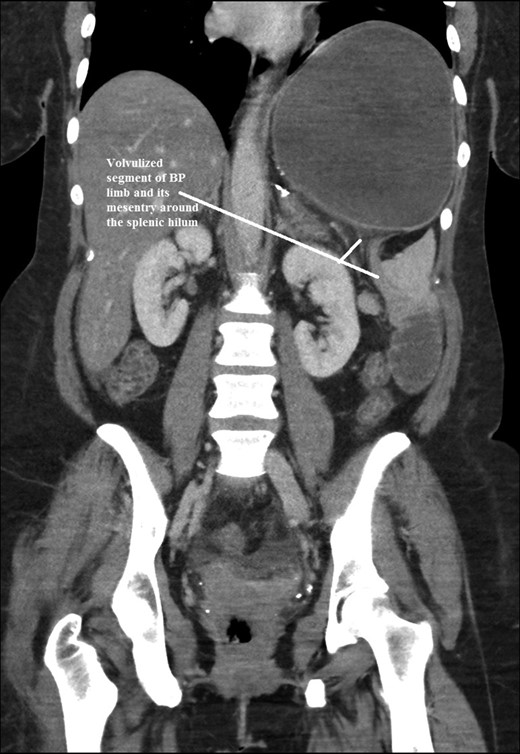

The intraoperative findings were not consistent with the radiological findings (Figs 1–4). As shown in the CT scan of abdomen and pelvis; multiple loops of dilated small bowel were seen, more predominantly dilated and matted bowel complex just above the spleen. The dilated bowel complex was decompressed using needle aspiration to help reduction of the bowel loops. The ileo cecal junction was then identified and traced back to the perisplenic hilar region. The trifurcation of three bowel loops (Roux limb, biliopancreatic limb and common limb) were identified with identification of ligament of Treitz. The prior gastric bypass was of ante colic- ante gastric type and Peterson’s defect was not closed. The above described bowel trifurcation had sunken postero- inferior to the spleen and had herniated through a potential space underneath the spleen and torsed around the splenic vessels and hilum. This picture was consistent with perisplenic small bowel volvulus. As noted earlier there was a massively dilated proximal small bowel segment above the spleen, displacing it caudally. Careful adhesiolysis was performed inferior to the spleen to release the segment of the trifurcation. The bowel segments once reduced were assessed and appeared viable. Of note, the spleen appeared better perfused after reduction. The remnant hernia defect of size 2 × 3 × 2.5 cm around the hilar region was then approximated using interrupted non-absorbable sutures. Enterotomy at the decompression site was closed with non absorbable suture. All potential sites of IH were re-examined and there was no evidence of any other internal herniation. Coelomic cavity was thoroughly irrigated and operation concluded successfully. Postoperative hospital stay was uneventful, and the patient was discharged home after two days.

Coronal CT scan of abdomen and pelvis showing Volvulized segment of bilio-pancreatic limb and its mesentery in the spleen hilum.